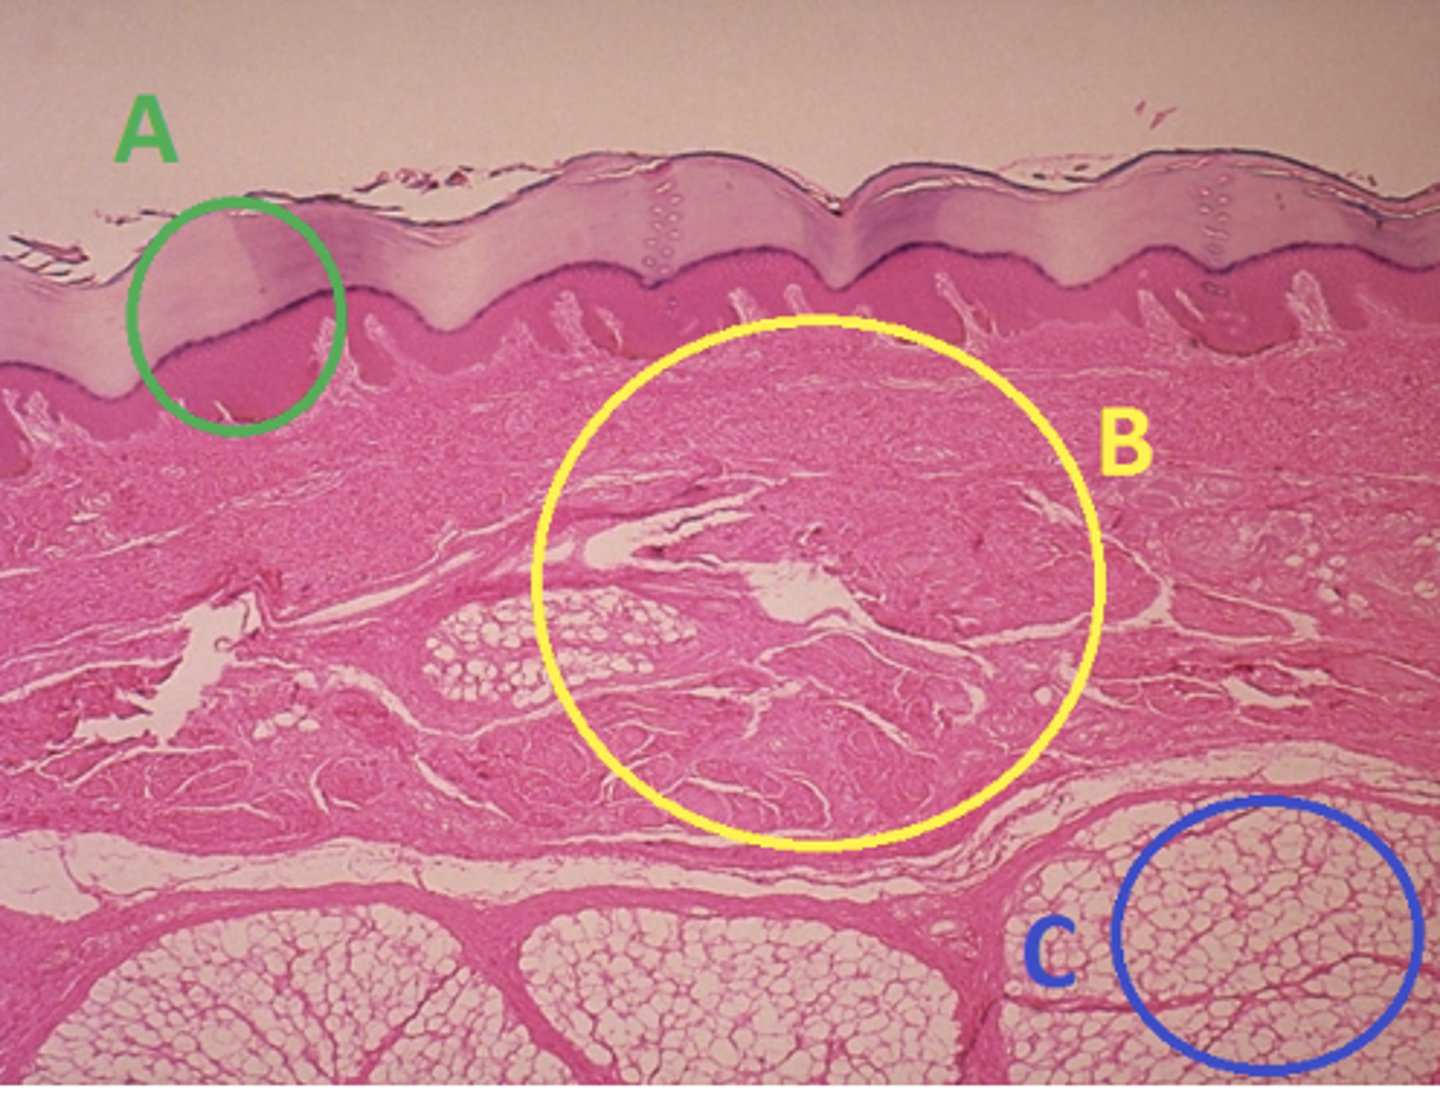

C - hypodermis

Answer the following questions based on the features indicated in the following image. Which letter indicates the administration site for subcutaneous injections?

A - epidermis

Answer the following questions based on the features indicated in the following image. Which letter indicates the administration site for topical creams and ointments?

B - Dermis

Answer the following questions based on the features indicated in the following image. Which letter indicates the administration site for the tuberculin skin test?

A - epidermis

Answer the following questions based on the features indicated in the following image. Which letter indicates a region of the skin with no nerves or blood vessels?

B - Dermis

Answer the following questions based on the features indicated in the following image. Which letter indicates the region where skin appendages (sweat glands, sebaceous glands, and hair follicles) have their roots?

Epithelial tissue

Answer the following questions based on the features indicated in the following image. Which of the four major tissue types is indicated by letter A?

Skin of the soles of the feet

Where would hair follicles be absent?

Skin in the axilla (armpit)

Skin on the back of the hand

Skin of the dorsal surface of the feet

Skin of the soles of the feet

C

Which letter indicates the administration site for insulin injections?

A

Which letter indicates the administration site for a lidocaine patch?

B

Which letter indicates the administration site for an allergy test?

B

Which letter indicates a region of the skin rich in dense, irregular connective tissue?

C

Which letter indicates the region most important for energy storage and thermal insulation?

Connective

Which of the four major tissue types is indicated by letter C?

Skin of the dorsal surface (back) of the hand

Which part of the body could the previous image represent?

Skin of the ventral surface (palm) of the hand

Skin of the dorsal surface (back) of the hand